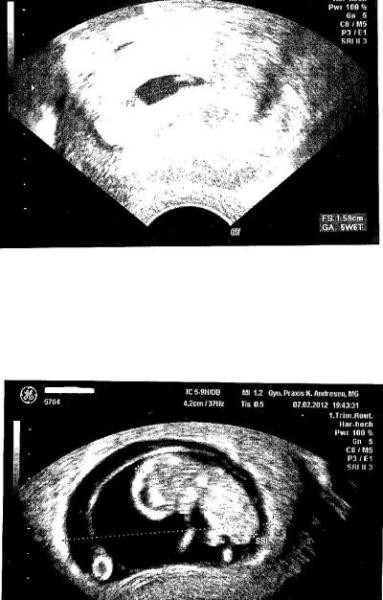

das erste Bildchen war in der 6 Woche und das zweite in der 9W4T.... wie schnell sich doch alles entwickelt....